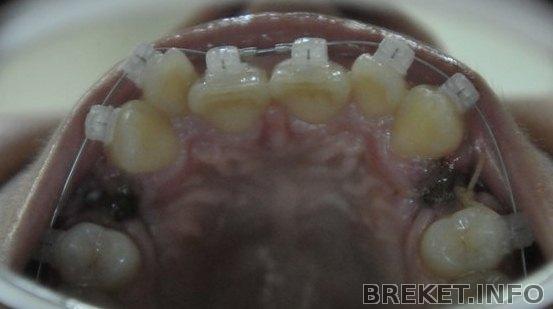

ПРОШЛО 5,5 МЕСЯЦЕВ *-* (Должна была 18 месяцев носить)

А уже завтра приклеивают ретейнеры , а через неделю уже снимаем *-*

блин , думала , что все намного дольше будет , а тут за 6 месяцев *-*

пропускаем квадратную дугу

вот фото , не идеал , конечно , но сказали , что верх не сдвинется, т.к. места нет

5_m-c_vch.jpg

5m-c_nch.jpg